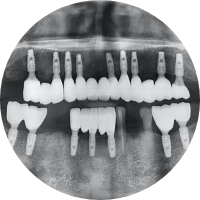

전악 임플란트, R2 게이트

• 치아 전체를 바꿨지만,

일상은 더 자연스러워졌습니다.

최첨단 기술을 통해 구강 상태를 면밀히 분석 후,

잇몸과 뼈 구조까지 과학적으로 설계하여 저작기능과 심미적인 효과를 함께 기대할 수 있습니다.

당신의 마지막 치아 치료, 목포미르치과병원이 함께합니다.

전체 임플란트 Before&After

• 2016.08.23 - 2016.09.04 - 2020.06.17

Before

After

After 4년 뒤